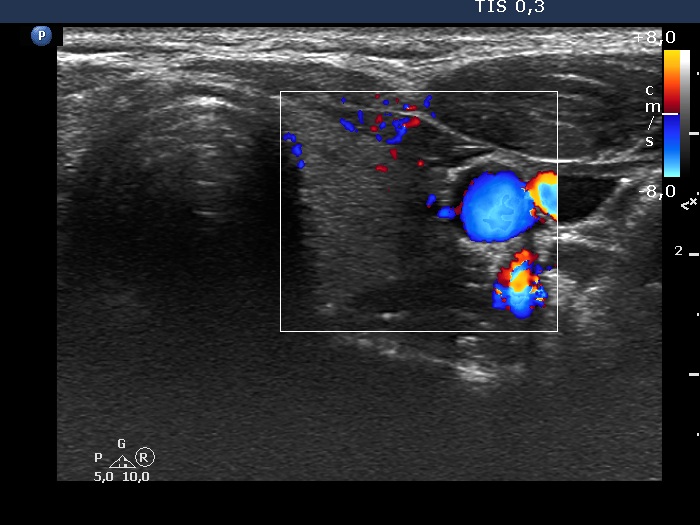

Four months after the previous examination (ultrasonographic picture 6)

Left lobe, transverse scan, color Doppler mode. The vascularity remained unchanged.